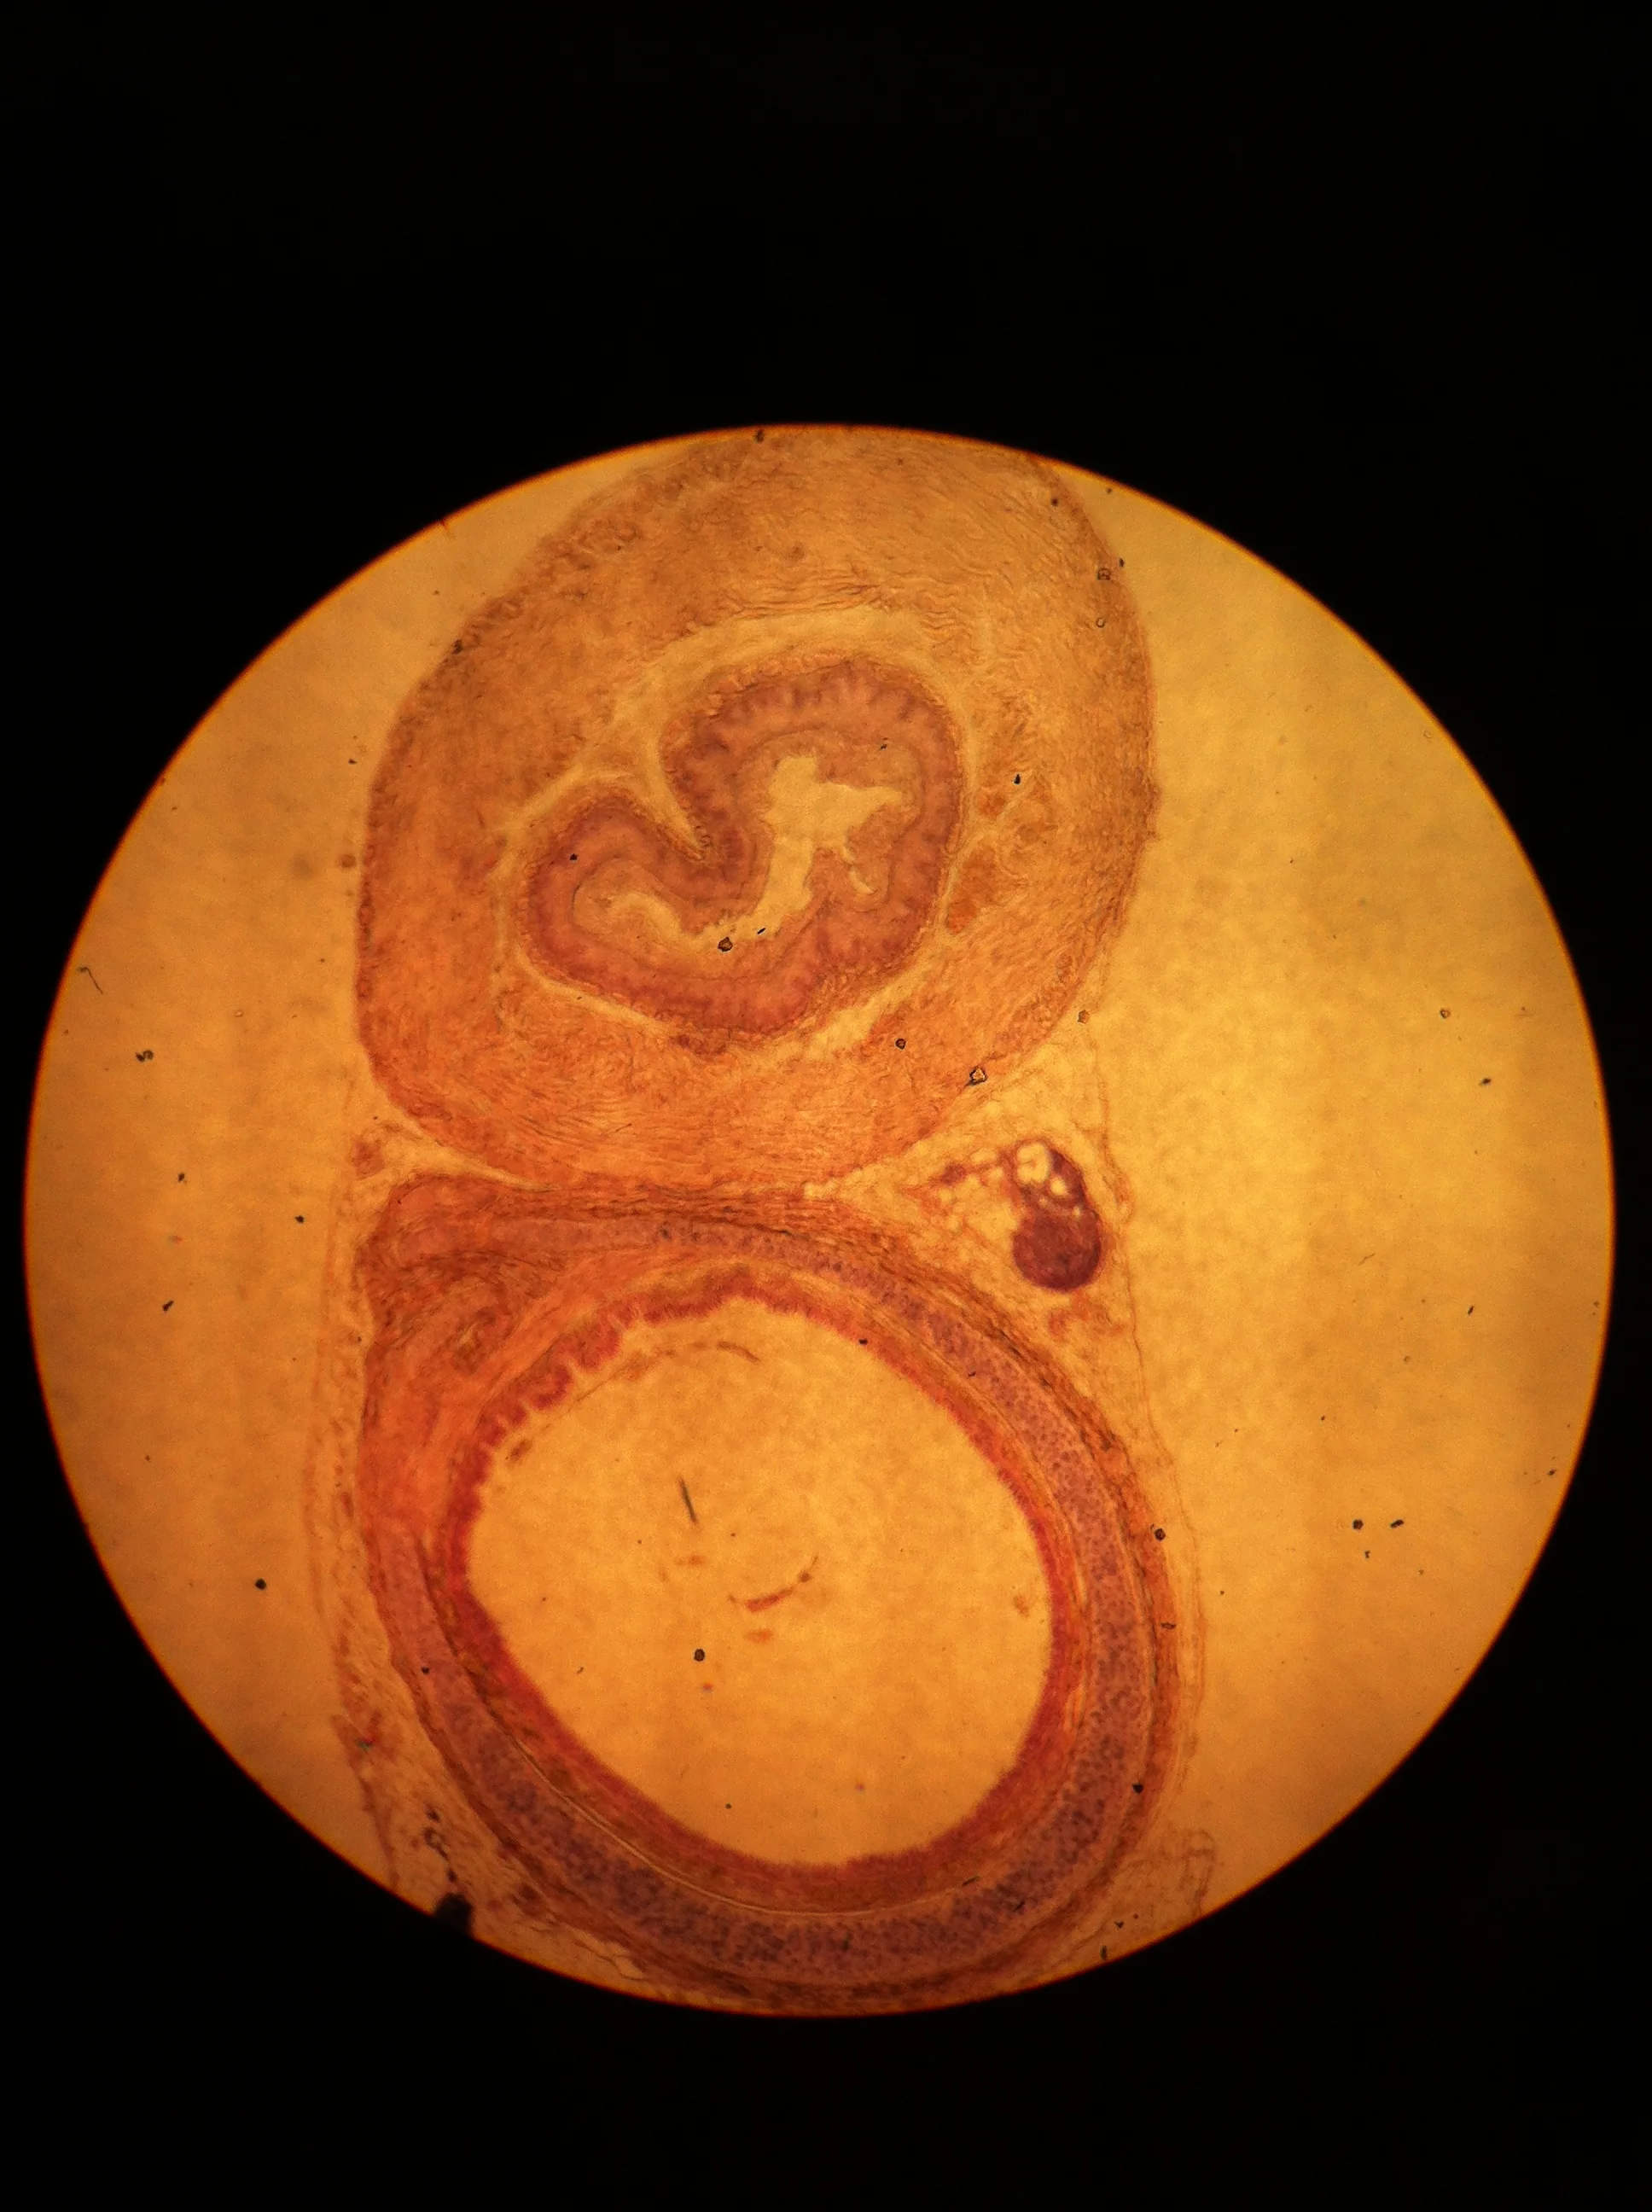

Trachea and Esophagus 40X